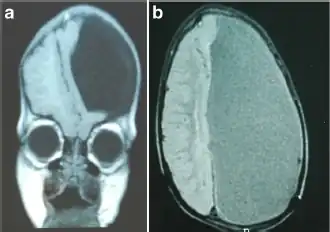

| a) MRI sagittal T1 scan demonstrating a left-sided hemihydranencephaly b) coronal | |

Hemihydranencephaly is a severe cephalic disorder characterized by complete or almost complete absence of the cerebral cortex with preservation of meninges, basal ganglia, pons, medulla, cerebellum, and falx. It is a special type of hydranencephaly.